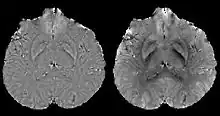

COSMOS assumes a model-free susceptibility distribution and keeps full fidelity to the measured data. This method has been validated extensively in in vitro, ex vivo and phantom experiments. Quantitative susceptibility maps obtained from in vivo human brain imaging also showed high degree of agreement with previous knowledge about brain anatomy. Three orientations are generally required for COSMOS, limiting the practicality for clinical applications. However, it may serve as a reference standard when available for calibrating other techniques.

MEDI has also been validated extensively in phantom, in vitro and ex vivo experiments. In an in vivo human brain, MEDI calculated QSM showed similar results compared to COSMOS without statistically significant difference.[15] MEDI only requires a single angle acquisition, so it is a more practical solution to QSM.

Thresholded k-space division[12][17] only requires a single angle acquisition, and benefits from the ease of implementation as well as the fast calculation speed. However, streaking artifacts are frequently present in the QSM and the susceptibility value is underestimated compared to COSMOS calculated QSM.